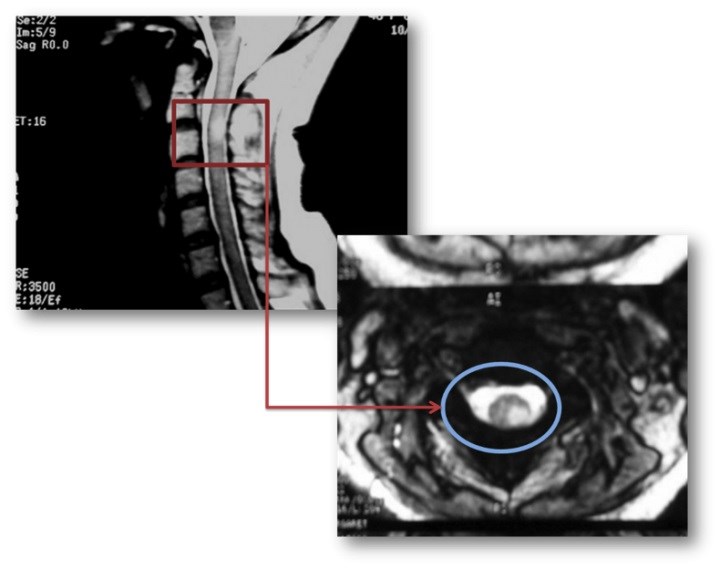

Spinal kord lezyonları

Spinal kord lezyonları, beyin MRG’sinde görülen lezyonların yaklaşık onda biri kadar sıklıkta olsa da, klinik açıdan son derece önemlidir. MS’li hastalarda spinal MRG incelemesi yapıldığında olguların yaklaşık %75’inde anormallik saptanır.

Kranial MRG’nin normal olduğu, ancak spinal MRG’de lezyon saptanan hastalarda MS tanısı daha dikkatle değerlendirilmelidir (bu oran %8–20 arasındadır). MS’i düşündüren spinal MRG özellikleri özetle şöyledir:

- Lezyon uzunluğu < 2 vertebra korpus segmenti,

- Sagital kesitte kord alanının %50’sinden küçük tutulum,

- Orta servikal ve torasik seviyelerde, periferal yerleşim,

- Asimetrik, multipl ve saçılmış lezyon dağılımı,

- Lateral / dorsal tutulumun anterior tutulumdan daha sık olması,

- Akut lezyonlarda ödem bulguları,

- Uzun dönemde fokal veya diffüz spinal kord atrofisi.

Bu özellikler, İMG – MRG-8 ve İMG – MRG-9 görsellerinde örneklenmiştir.

İMG – MRG-8: Spinal kord lezyonları.

İMG – MRG-9: Spinal kord lezyonları.